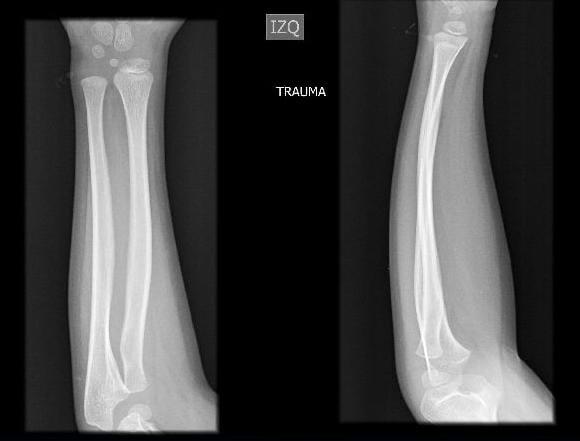

Introducción: Las deformidades plásticas son afecciones raras, que afectan principalmente a pacientes en edad pediátrica, quienes presentan microfracturas que resultan en deformación de la diáfisis del hueso afectado, sin ser macroscópicamente visibles. Caso clínico: Se presenta el caso de un paciente masculino de 6 años, quien presenta caída desde su propia altura mientras jugaba fútbol, con posterior fractura por plástica en la diáfisis del radio y cúbito izquierdo, por lo que se le realiza tracción contratación y reducción cerrada, con radiografía control qué evidencia alineación con adecuada reducción. Discusión: Las fracturas por deformidad plástica son infrecuentes, su diagnóstico podría pasar desapercibido teniendo en cuenta que la clinica no en todos los casos es evidente, el manejo debe realizarse de manera integral, con el fin de disminuir las complicaciones. Conclusión: Las fracturas por deformidad plástica en antebrazo son entidades raras y se presentan casi exclusivamente en pacientes pediátricos, se recalca la importancia de ser reconocidas por la población médica, para de esta forma brindar un tratamiento oportuno y adecuado a estos pacientes.